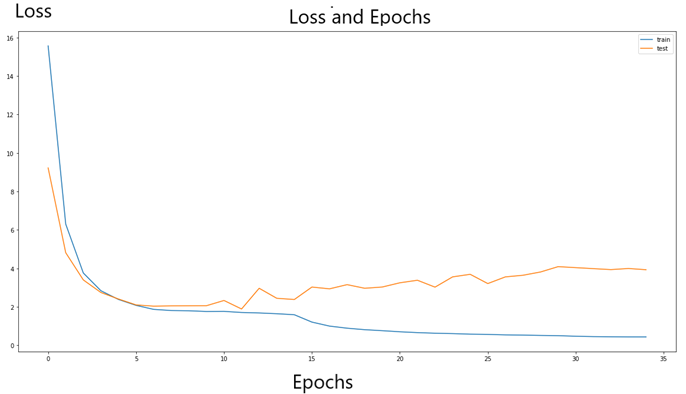

history=model.fit(x=[x_train1],y=[y_train1],batch_size=16,epochs=epochs,callbacks=[lr_call],validation_data=(x_valid,y_valid))Lets see our validation and training loss .

plt.figure(figsize = (20,10))

plt.title('Loss')

plt.plot(history.history['loss'], label='train')

plt.plot(history.history['val_loss'], label='test')

plt.legend()